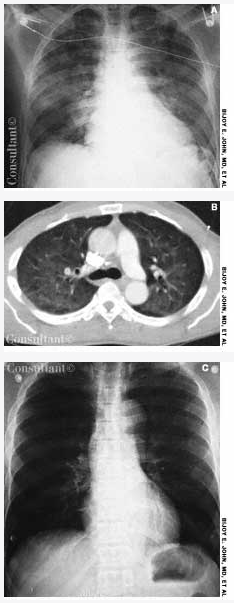

Bijoy E. John, MD; Amado Freire, MD

<p>A 58-year-old man with a history of a seizure disorder was hospitalized with acute-onset shortness of breath immediately following a tonic-clonic seizure. He was afebrile; in respiratory distress;...